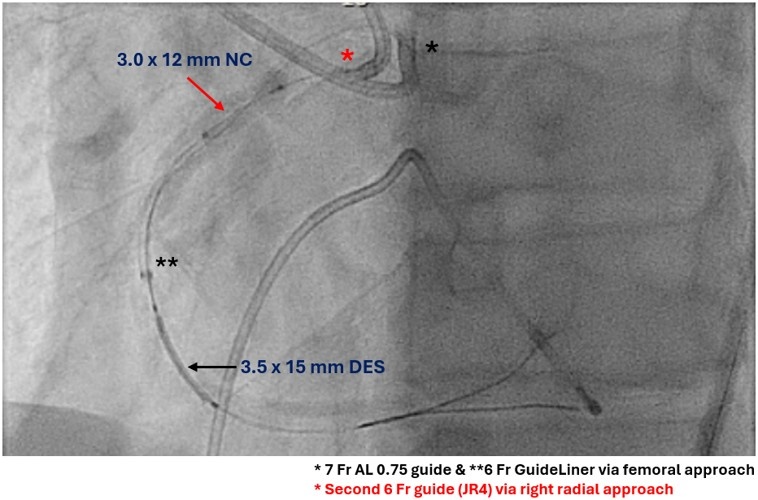

It was decided to use ping-pong guides for the modified tunnel-in-landslide technique (TILT). A second guide (6F JR4) engaged the RCA from the radial approach, and a 3.0-mm balloon was inflated in the proximal RCA to trap the 6F guide extension (GE) (Figure 3). With this maneuver, the operator was successfully able to deliver the balloons and stent (Figure 3, Video 1), followed by a larger (4.0-mm) IVL balloon. The final angiogram (after stenting the remaining RCA) showed a good result, with an intravascular ultrasound minimal stent area of 7.5 mm² (Figure 4, Video 2).

TILT facilitates equipment delivery through a GE (“tunnel”) pinned by inflating a balloon between the vessel wall and the GE (“landslide”).1 The original technique used single 8F arterial access with a 5F GE,1 which can be modified using ping-pong guides (the second guide is used to deliver the “blocking” balloon), both of which can be 6F or 7F.2,3 This requires dual arterial access that is either already in place (eg, chronic total occlusion PCI) or can be obtained (eg, radial-to-femoral for complex ad-hoc PCI). This technique facilitates equipment delivery when conventional approaches fail.